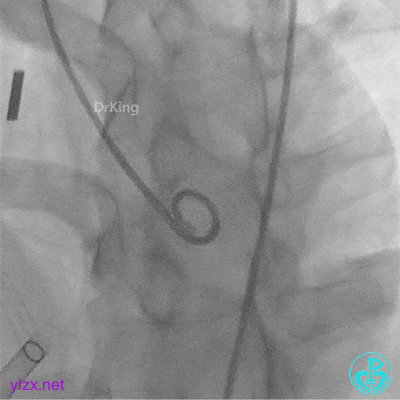

左盘展开

右盘展开并左右盘面骑跨于室间隔两侧

封堵器完全释放后位置、形态观察

封堵器完全释放后盘面平整,呈“工”字型骑跨于室间隔两侧,未见瓣膜影响。